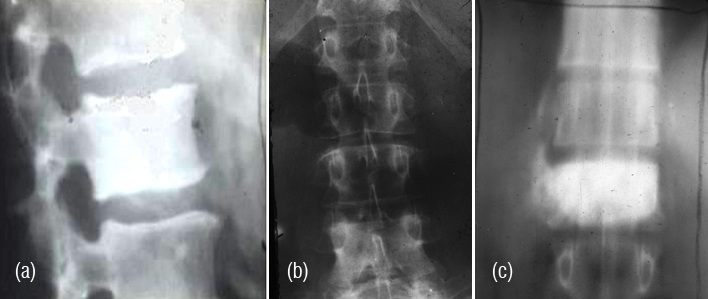

This is also a rare tumor and may involve the vertebral column. Radiological findings include lytic lesion with sclerosis and cartilaginous calcifications (Figure 9abcd). CT helps in identification of early calcifications. CT allows optimal detection and characterization of matrix mineralization, endosteal scalloping. MR imaging depicts the extent of marrow involvement and demonstration of soft tissue extension with mass formation. MRI shows the cartilaginous nature of the lesion by bright signals in T2 (Figure 10abcd).

Figure 9a,b: Chondrosarcoma of L1. Note the paravertebral ring like calcifications.

Figure 9: Chondrosarcoma of L5- (c) AP view, (d) Lateral view.

Figure 10: Chondrosarcoma L5 – (a) plain films, (b) CT helps in identification of small calcifications. (c) plain, (d) MRI.